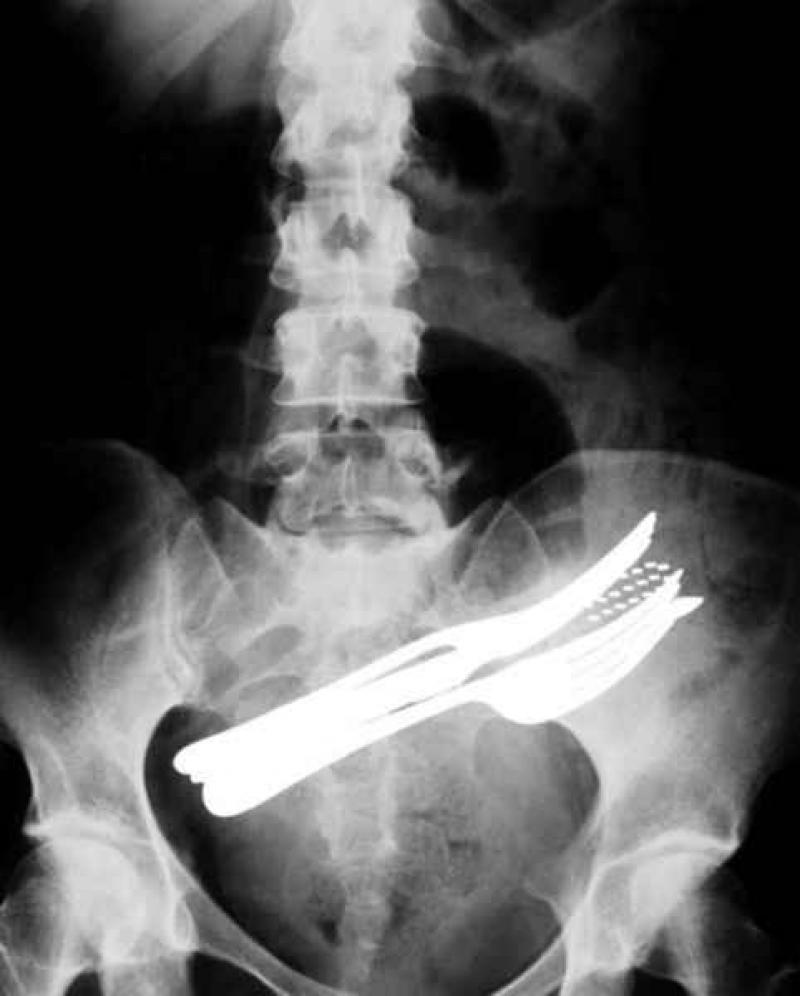

Röntgenfoto's zijn een medische uitvinding die ons al decennia lang helpt. Ze geven een nieuw gezichtspunt als het gaat om het vinden en behandelen van inwendige verwondingen. De machines kunnen opmerkelijke beelden vastleggen van het menselijk lichaam en ze documenteren vaak gruwelijke verwondingen. Een wonde van iemand zien, is al erg, maar als je ook kan zien wat de schade in het lichaam is, dat is nog veel erger. We hebben 12 tegelijk fascinerende, gruwelijke en hilarische röntgenfoto's op een rijtje gezet. Stel jezelf maar eens de vraag hoe iemand ooit aan die verwondingen is gekomen. We beginnen nog rustig.